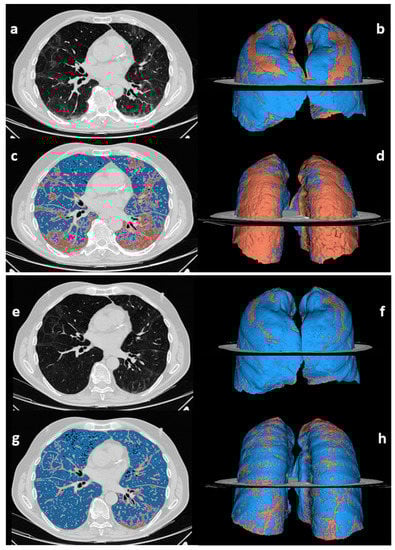

| No. of abnormal chest CT scans | 49/63 (78%) | 48/63 (76%) * | 1.000 |

| % of compromised lung volume | 14.4 [10.6–21.2] | 12.3 [9.2–15.9] | <0.001 |

| Type of CT pattern | 0.038 | ||

| GGO | 8 (16) | 2 (4) | |

| Reticular | 31 (63) | 38 (79) | |

| Combined | 10 (21) | 8 (17) | |

| Improved (Group 3), n = 40/47 | Stably Abnormal (Group 4), n = 7/47 | |||

|---|---|---|---|---|

| 3 Months | 12 Months | 3 Months | 12 Months | |

| Compromised lung volume % | 15.6 [11.0–21.7] | 12.0 [9.2–14.3] | 12.1 [10.9–20.5] | 16.6 [11.8–19.7] |

| Type of CT pattern | ||||

| GGO | 6 (15) | 2 (5) | 1 (14) | 0 (0) |

| Reticular | 28 (70) | 34 (85) | 2 (29) | 3 (43) |

| Combined GGO- reticular | 6 (15) | 4 (10) | 4 (57) | 4 (57) |